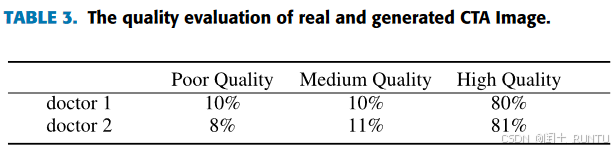

评估了200个病人的CTA影像,其中100例是模型生成的,另外 100例是真实CTA。两种数据混合后由两名放射医师独立进行打分。具体评估的方面包括血管壁清晰度、血管连续性、血管边界、小血管清晰度、颅内软组织和伪影等。打分1~3,分数越高表示图像质量越高。100例生成CTA的评估结果如下图所示: